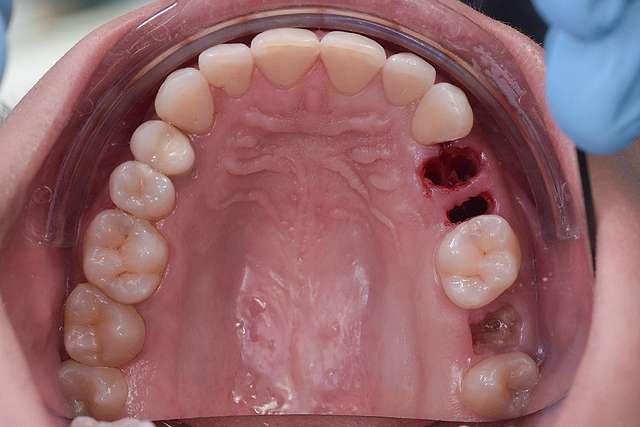

Dental implants are treatments designed for teeth that we can no longer save. Dental implants rely on the principle of osseointegration, or in other words, on the implant being integrated in the bone. For a long period of time, this was the main objective of the industry. Osseointegration, placing implants in relation to bone. Today , we know that osseointegration is extremely predictable and we focus on key elements that can make the difference in the quality of the end result.

Guided surgery, for one, facilitates an ideal pre-planned position, in relation to available bone, and even more important, in relation to the future implant supported crown. Guided surgery translates into increased precision, which means safer surgeries, reduced surgery time, and reduced trauma. Also the focus of these types of treatments is shifted towards tissue reconstruction, which on the long run, has a far greater impact esthetically and biologically. Tissue stability means implant longevity. This case is a relevant example for this type of approach towards implant dentistry.